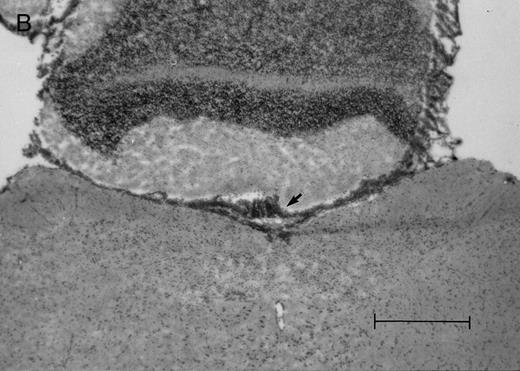

Histologic progression of leukemic meningitis. All sections are 12-μm coronal sections. (A) Cisterna magna at 14 days postinjection showing a small cluster of HPB-ALL cells (arrow) in the subarachnoid space, H&E, bar = 0.64 mm. (B) Cisterna magna at 21 days postinjection showing large groups of HPB-ALL cells in the subarachnoid space (arrow), H&E, bar = 0.64 mm. Compare the large groups of cells shown here with the small cluster at 14 days postinjection shown in (A).

In the timed histologic study, animals were killed sequentially postintrathecal HPB-ALL cell injection. Three animals each at 1, 2, 4, 7, 11, 14, and 19 days, two animals at 20 days, and seven animals at 21 days postinjection underwent CSF sampling and were immediately killed. At the 19 day time point, only CSF was sampled, as the same group of animals was also sampled and then killed as part of the 21 day time point. On histologic examination, brain sections from animals killed between 1 and 11 days postinjection showed rare, dispersed leukemic cells in the subarachnoid space at both the cerebral and cerebellar levels. At day 14, very small clusters of HPB-ALL cells could be observed in the subarachnoid space at the cerebellar level in two of three animals (Fig 2A). By 21 days postinjection, large groups of cells could be seen in the subarachnoid space of all animals in the cerebellar sections (Fig 2B). Collections of leukemic cells were concentrated in the most posterior cerebellar sections, in the meninges of the cisterna magna. Small clusters of leukemic cells or scattered leukemic cells were observed in the subarachnoid space of cerebral sections (Fig 2C and D). In animals that developed symptoms during the course of the natural progression of leukemic meningitis, there was extensive infiltration of the subarachnoid space by leukemic cells throughout the brain, with the most dense involvement in the basal region. This was accompanied by permeation of the Virchow-Robin spaces (Fig 2E). The pattern was strikingly similar to leukemic meningitis in humans.